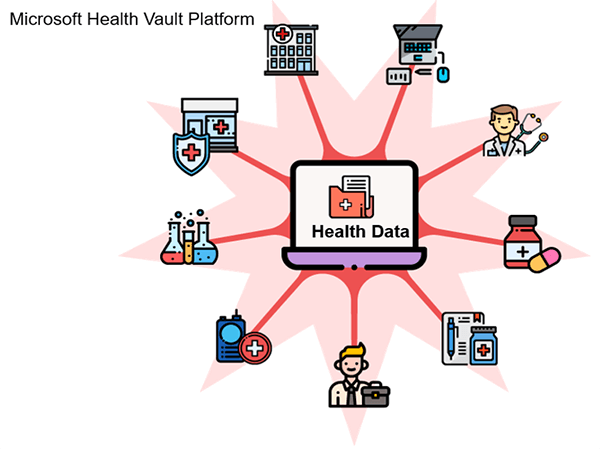

It is important to recognize the acronyms for terminology used when discussing Informatics. Biomedical Informatics (BMI) refers to platforms that are used for medical purposes such as patient care. A picture archiving and communication system (PACS) denotes a BMI platform which is configured in a manner that facilitates storing, retrieving, and distributing medical images.

A hospital information system (HIS) and a radiology information system (RIS) encompass BMI platforms used in a health-care facility and a radiology department. And finally, Electronic Medical Record (EMR) otherwise known as Electronic Health-care record (EHR) are electronic versions of a patient’s collection of medical documents.

PACS is usually an integration of input from digital devices which may be any radiological modality. These devices include Image acquisition device, image storage server for short or long term storage of data, transmission network, display station, imaging work station, and user interface, camera to convert to hard copies images on a need basis, and integration to radiology information system and hospital information system.

A picture archiving and communication system (PACS) is a medical imaging technology that provides economical storage and convenient access to images from multiple modalities. The universal format for PACS image storage and transfer is DICOM (Digital Imaging and Communications in Medicine). Combined with available and emerging web technology, PACS can deliver timely and efficient access to images, interpretations, and related data. PACS is used by radiology personnel to manage the workflow of patient exams.

Electronic medical records (EMRs) are digital versions of the paper charts in clinician offices, clinics, and hospitals. EMRs contain notes and information collected by and used by clinicians in that office, clinic, or hospital. They are an electronic (digital) collection of medical information about a person that is stored on a computer. An EMR includes information about a patient’s health history, such as diagnoses, medicines, tests, allergies, immunizations, and treatment plans. They are mostly used by providers for diagnosis and treatment.